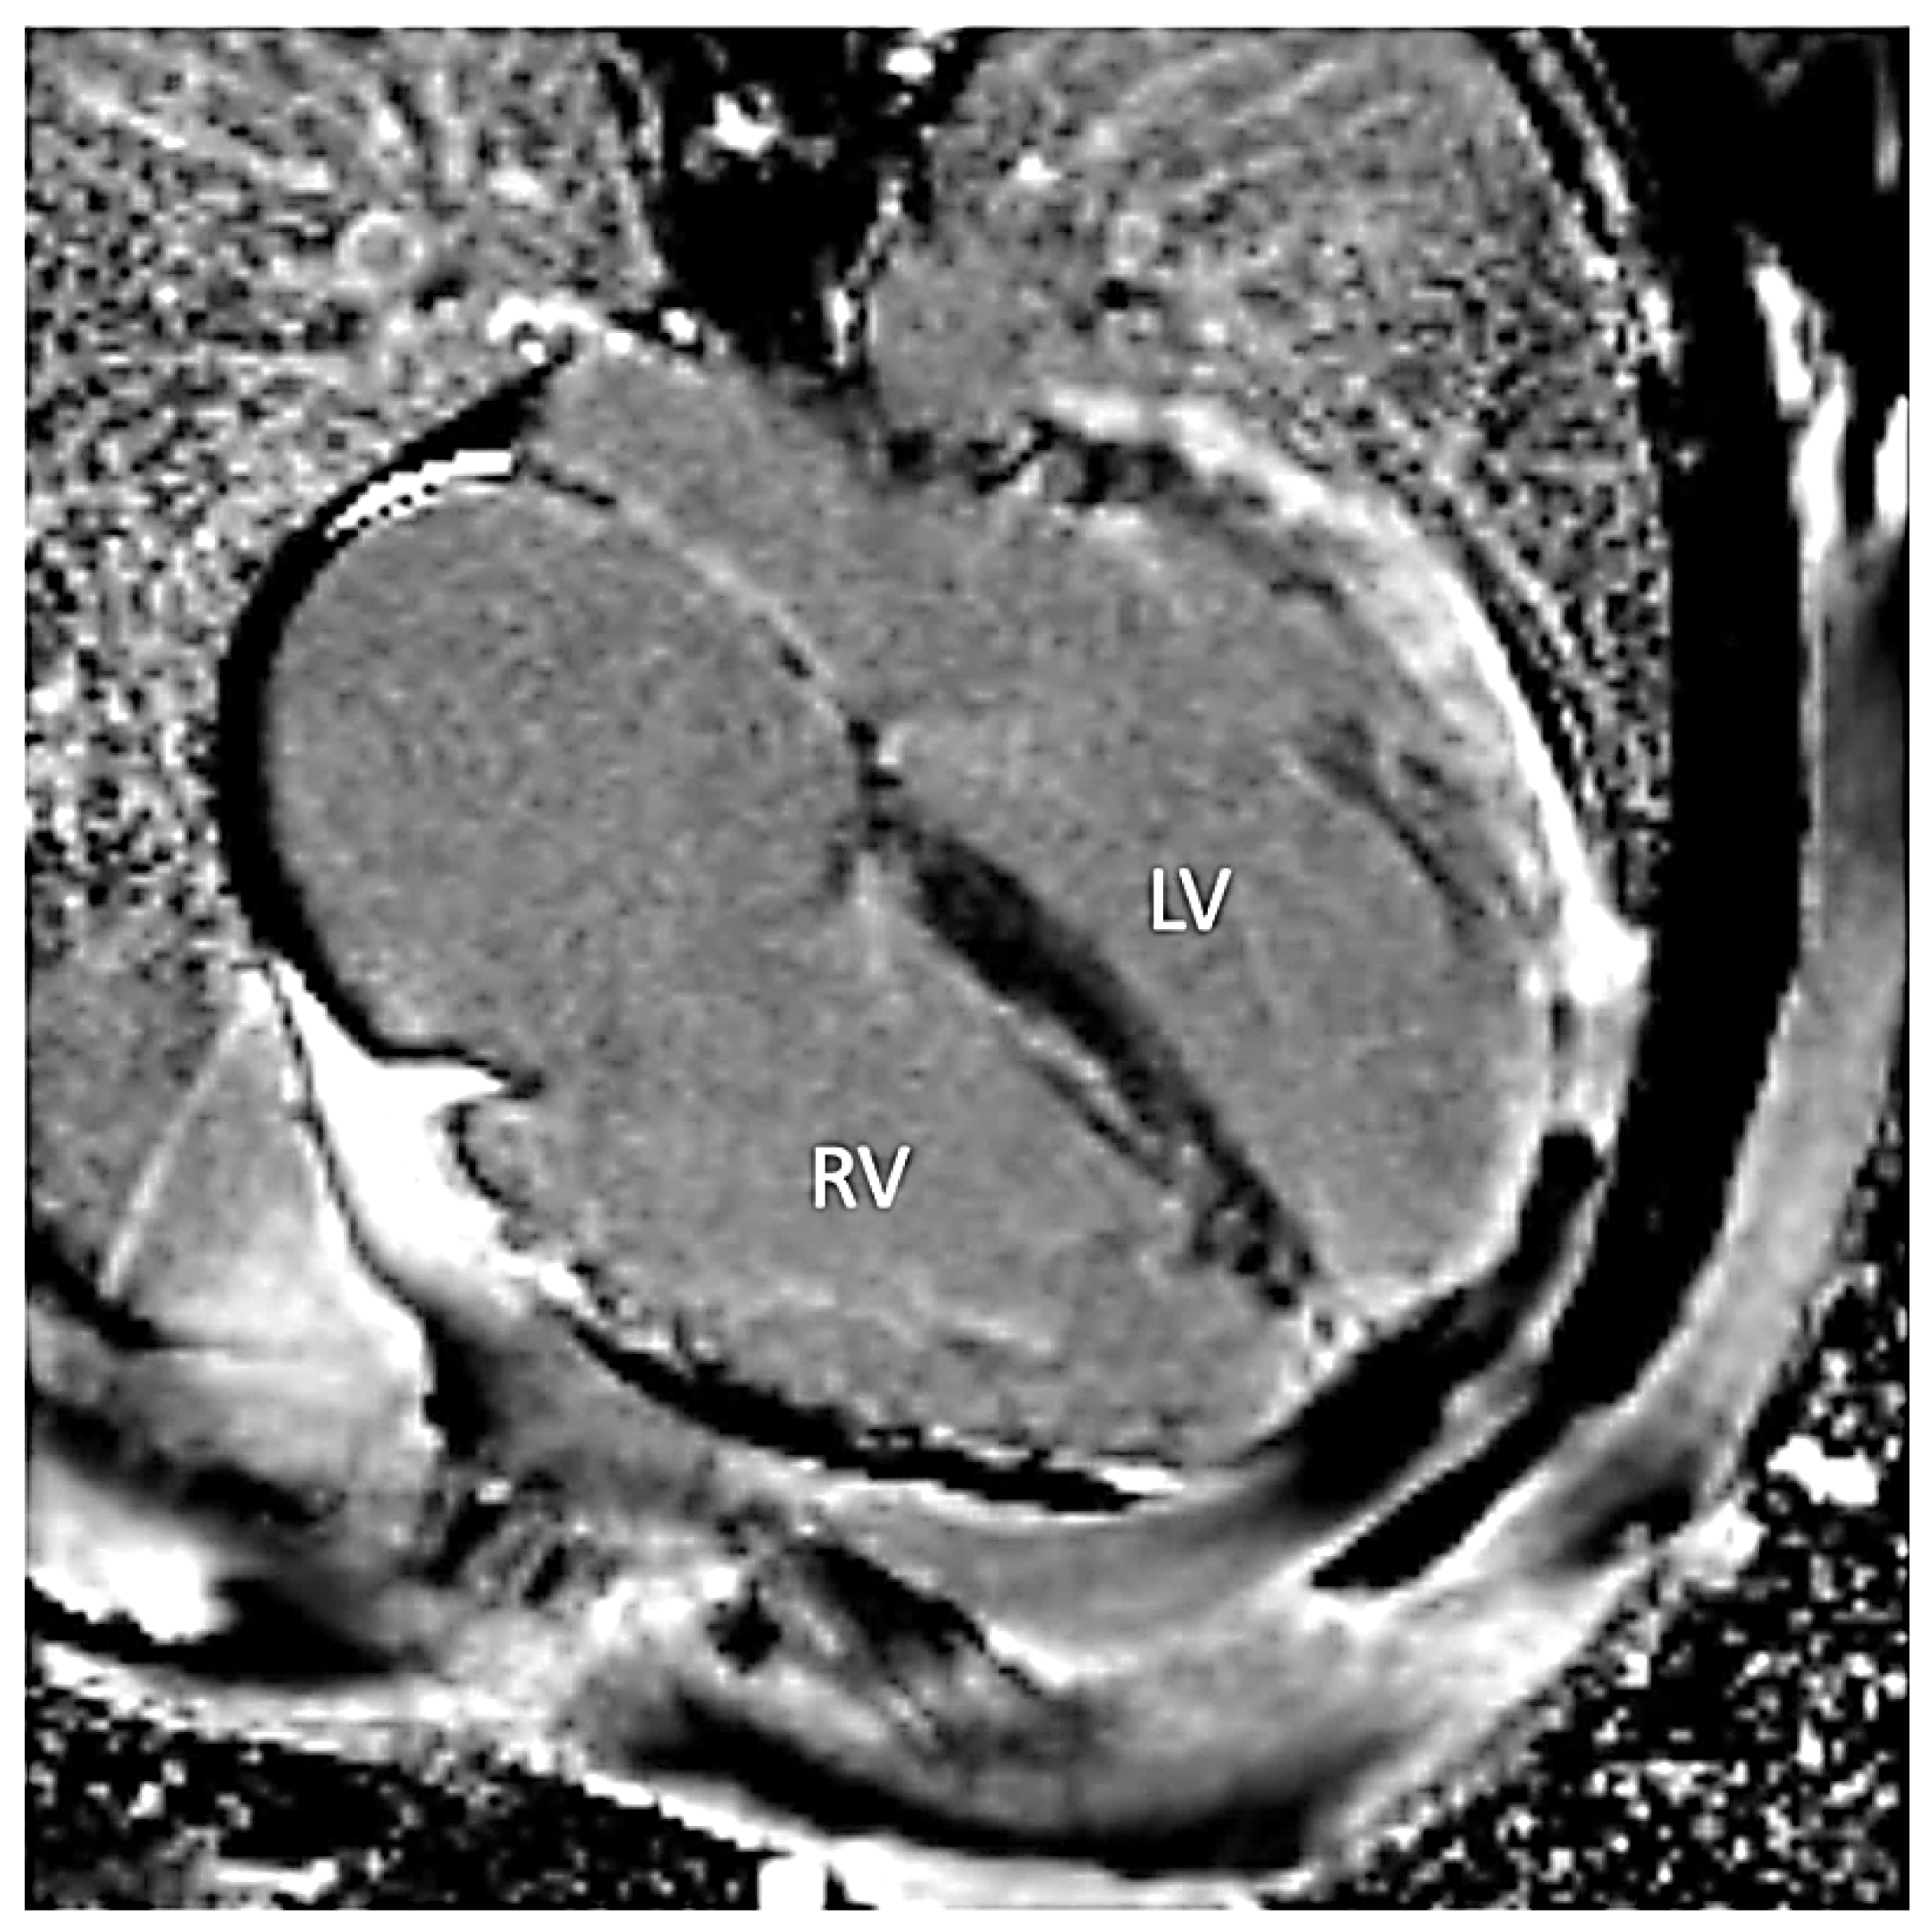

Figure 3.

Steady-state free precession short axis view demonstrating increased thickness of the interventricular septum (IVS) and thinning of the left ventricular lateral wall (arrow).